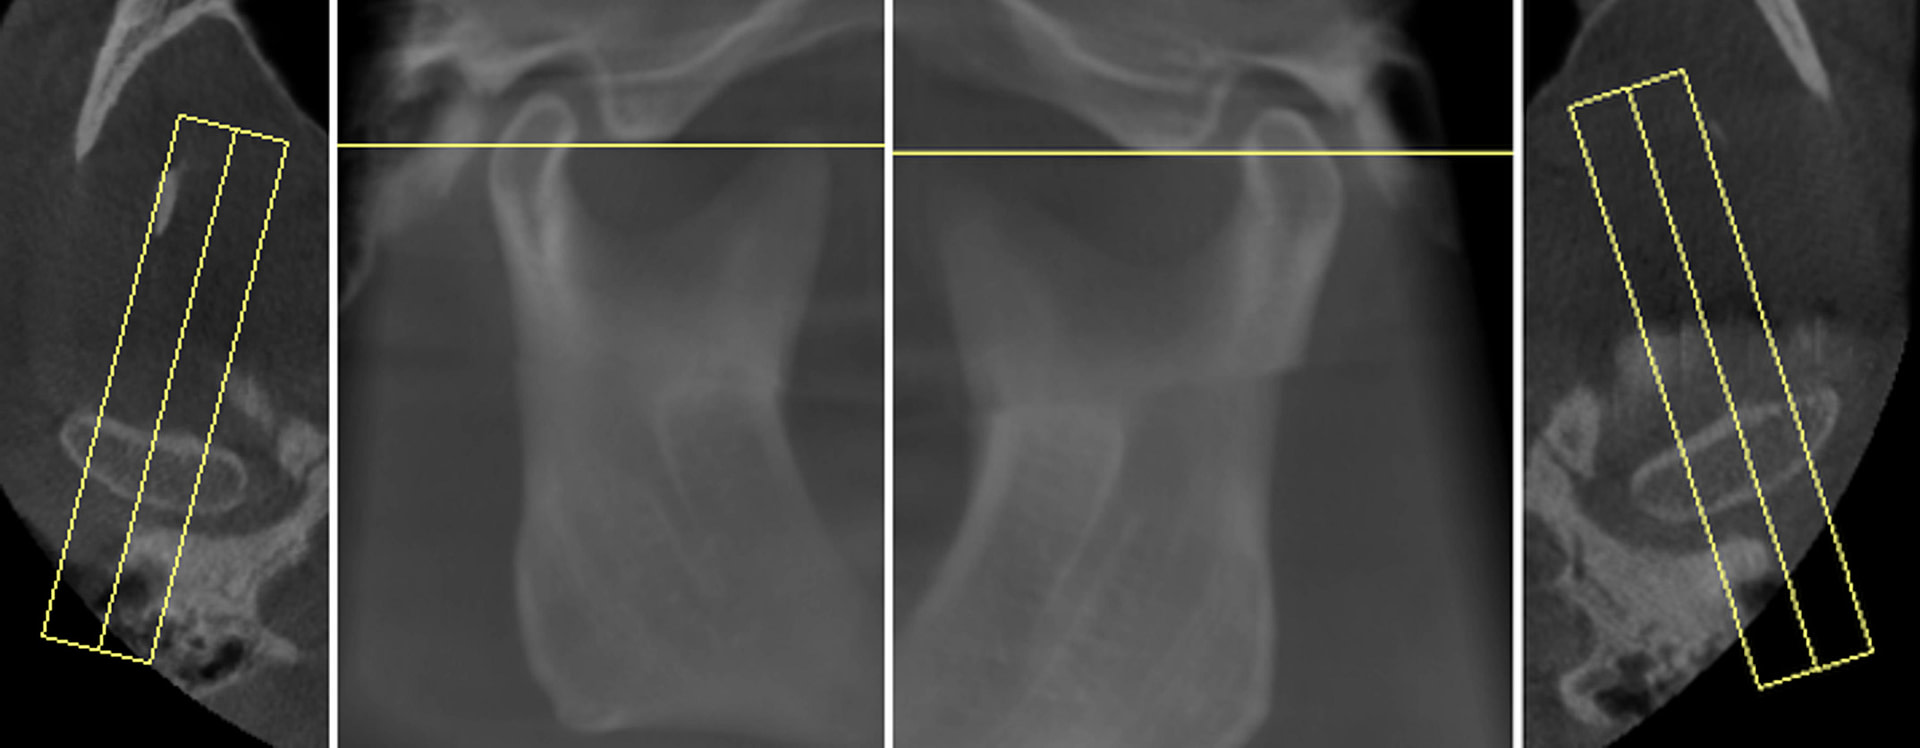

Tooth number is selected to analyze the root canal morphology within the CBCT radiograph.

Sagittal and coronal slices and highlighting the angle/curvature/length of the canals.

Measurement of periapical radiolucency volume is a unique advantage with 3D CBCT versus 2D PA. These are endodontic reports for tooth 12 which had a very large periapical radiolucency. The reports were done before and after a long-term calcium hydroxide dressing.